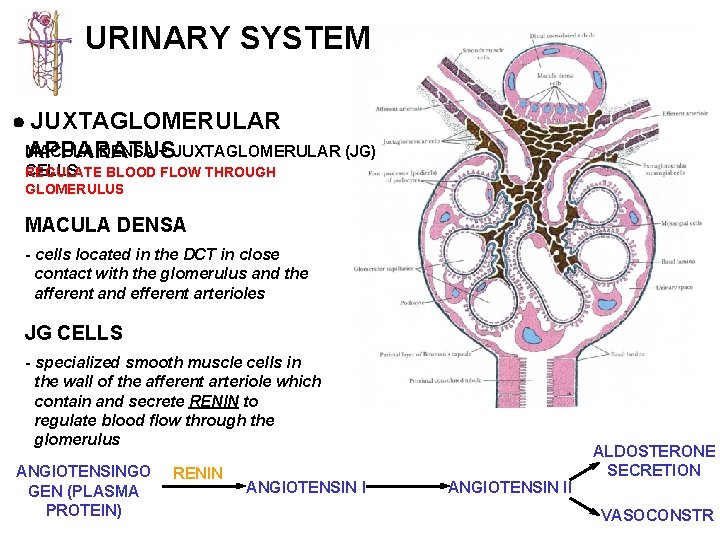

URINARY SYSTEM JUXTAGLOMERULAR MACULA DENSA + JUXTAGLOMERULAR (JG) APPARATUS CELLS REGULATE BLOOD FLOW THROUGH GLOMERULUS MACULA DENSA - cells located in the DCT in close contact with the glomerulus and the afferent and efferent arterioles JG CELLS - specialized smooth muscle cells in the wall of the afferent arteriole which contain and secrete RENIN to regulate blood flow through the glomerulus ANGIOTENSINGO GEN (PLASMA PROTEIN) RENIN ANGIOTENSIN II ALDOSTERONE SECRETION VASOCONSTR

URINARY SYSTEM JUXTAGLOMERULAR MACULA DENSA + JUXTAGLOMERULAR (JG) APPARATUS CELLS REGULATE BLOOD FLOW THROUGH GLOMERULUS BARORECEPTOR THEORY - assumes JG cells function as stretch receptors (high blood pressure would inhibit release of renin) MACULA DENSA THEORY - assumes the secretion of renin is regulated by the composition of the fluid in the DCT / afferent arteriole (low sodium would increase the release of renin) ANGIOTENSINGO GEN (PLASMA PROTEIN) RENIN ANGIOTENSIN II ALDOSTERONE SECRETION VASOCONSTR

URINARY SYSTEM JUXTAGLOMERULAR MACULA DENSA + JUXTAGLOMERULAR (JG) APPARATUS CELLS REGULATE BLOOD FLOW THROUGH GLOMERULUS ANGIOTENSINGO GEN (PLASMA PROTEIN) RENIN ANGIOTENSIN II ALDOSTERONE SECRETION VASOCONSTR